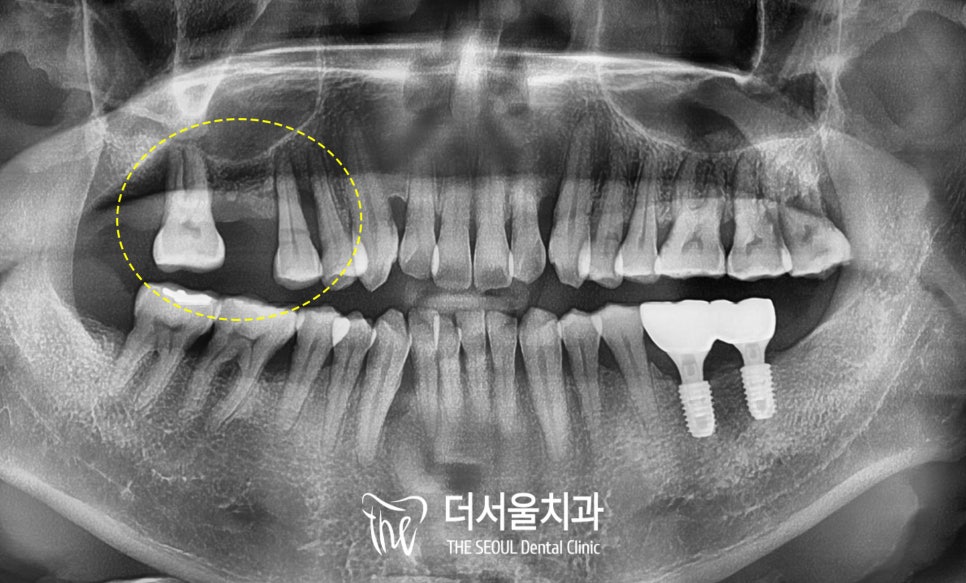

파노라마 엑스레이를 보면

제가 해드린 왼쪽 아래는

아직도 잘 유지되고 있는 상태였고,

이번에 불편하신 오른쪽 위를 살펴보면

어금니 하나가 빠져있습니다.

치근단 사진을 찍어서

잇몸뼈의 높이와

수술이 가능한 상황인지

자세히 살펴보면

결손된 어금니 자리는

상악동이 많이 내려와

함기화 되어있는 상황이었고,

양옆의 소구치와 대구치는

그 주변으로 치조골 소실이

심하게 관찰되었습니다.